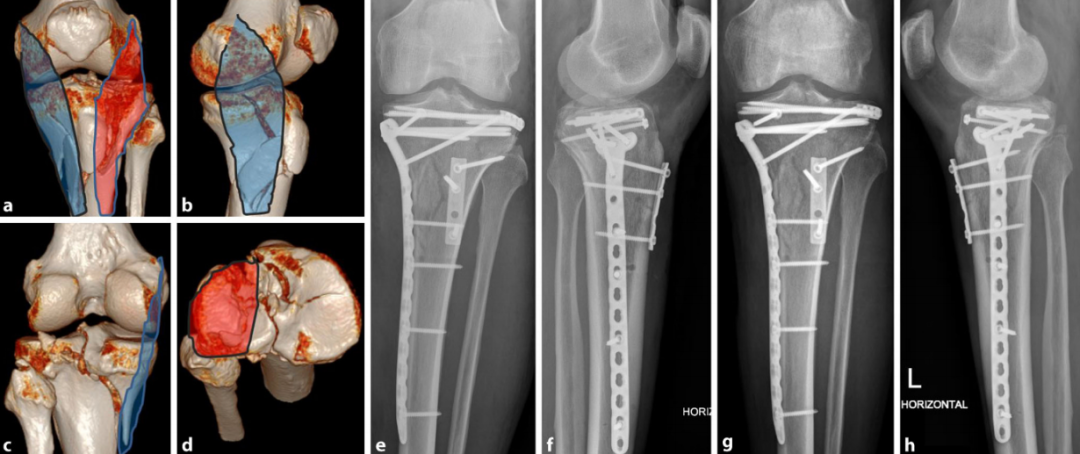

图15:a–d 术前计划CT(计算机断层扫描):外翻/伸展型骨折累及内侧柱、外侧柱及后柱。

-

仰卧位后内侧入路(蓝色)固定内侧柱。本例后柱为简单骨折,无需后侧支撑。

扩展前外侧入路(红色)显露外侧柱及胫骨平台外侧,固定胫骨结节骨折块并行平台支撑(Rafting技术)。

e, f 术后首次体位验证。g, h 术后10周随访影像。

病例2

图16:外翻/屈曲型骨折合并骨质疏松症,累及前柱、内侧柱及后柱。

俯卧位扩展后侧入路(罗氏入路,蓝色),安装后侧钢板。

调整为仰卧位(RL)后行扩展外侧入路(红色)。

a–d 术前计划CT(计算机断层扫描)。e, f 术后首次体位验证。

病例3

图17:屈曲型骨折累及后柱

俯卧位Lobenhoffer入路(蓝色标记区域)行后柱支撑固定,但关节内视野受限,导致后中央区(Krause分类PZ区)骨折块未实现解剖复位。

经皮固定胫骨平台外侧及内侧骨折延伸部分。

a–d 术前计划CT(计算机断层扫描)。e, f 术后首次体位验证。g, h 术后1年随访影像。

病例4

图18:后外侧柱孤立性骨折

俯卧位Carlson后外侧入路 或 Frosch入路后侧部分 行骨折固定。

a–d 术前计划CT(计算机断层扫描)。e, f 术后首次体位验证。g, h 术后1年随访影像(因前方螺钉尖端突出引起不适,已行内固定取出术)。